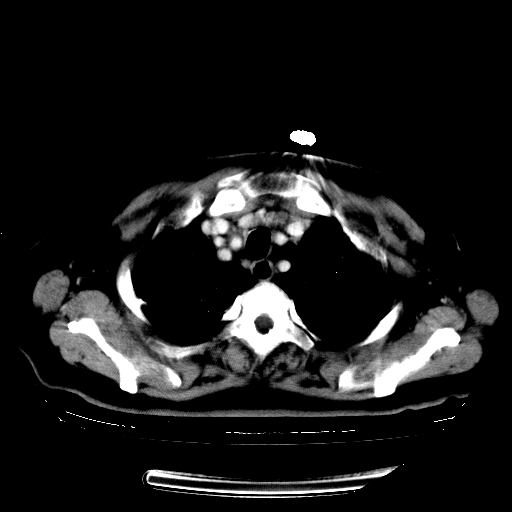

女,70岁,咳嗽、咳痰一个月,低热一周。

1.左上肺结核,部分纤维化。右肺中下叶部分肺不张,内见液化、坏死及点状钙化,右中下叶支气管壁增厚、管腔狭窄,见多个点状钙化,结合临床考虑支气管内膜结核,建议痰检查抗酸杆菌并参考血沉。两肺多个小圆点状高密度灶,境界模糊,多考虑结核肺内播散。但本人年龄较大首先应支气管镜检以除外右肺癌。

2.胸主动脉夹层。

支持,首先一元论解释。胸主动脉部分层面环形低密度,中心强化。环形影不强化。不象真假腔的改变。我考虑动脉炎,不太支持夹层动脉瘤-和大家的观点不一致,希望楼主让患者再做个心血管的彩超吧。